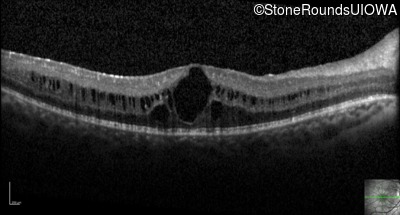

Optical Coherence Tomography - Right - 20/25

Exemplar / OCT Stack

OCT Stack